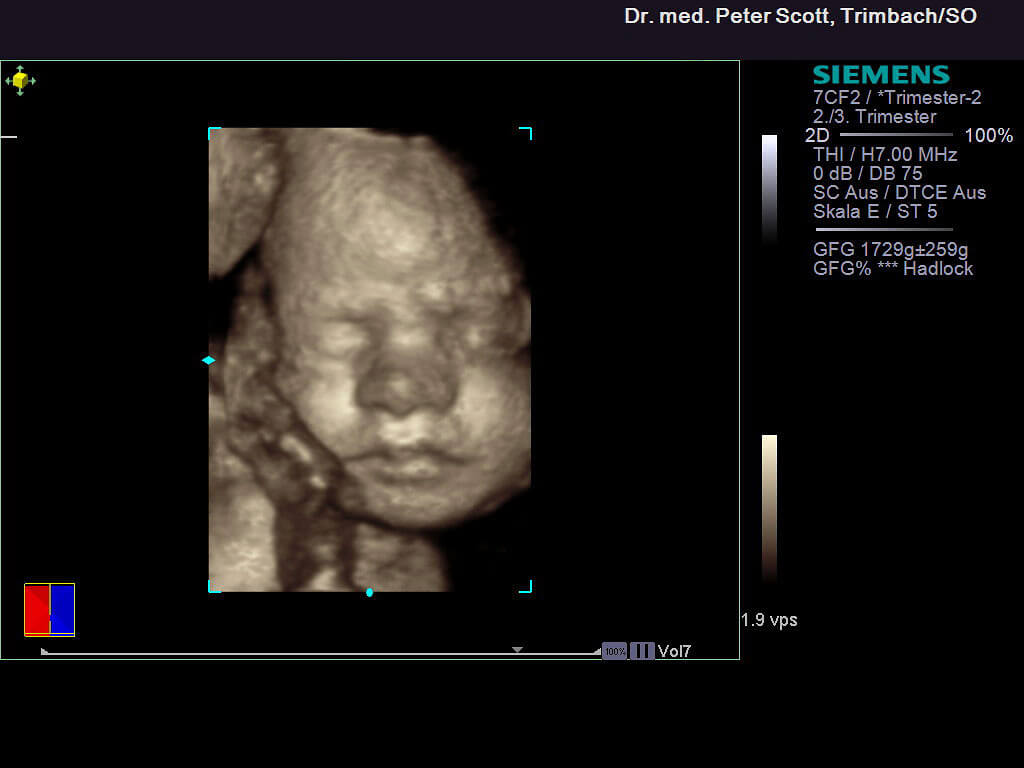

4 D Ultraschall

• Ergänzende Untersuchung, wirklichkeitsnahe dreidimensionale Bilder

• Benötigt gute Bedingungen (ideale Lage des Kindes, Fruchtwassermenge)

• Bringt meist keine zusätzliche Information (z.B. Missbildungen)